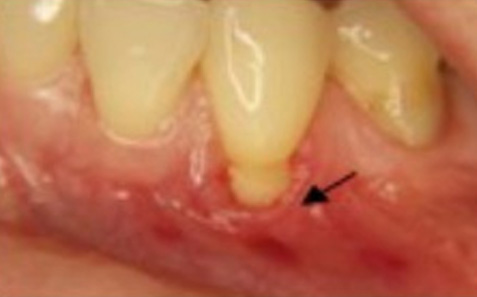

1. Gum Grafting: Gum grafting is a common surgical procedure used to repair gum recession. During the procedure, Dr. Ghayoumi takes gum tissue from another area of your mouth, such as the palate or adjacent gum tissue, and grafts it onto the affected area. This helps to cover the exposed tooth roots and restore a healthy gumline.